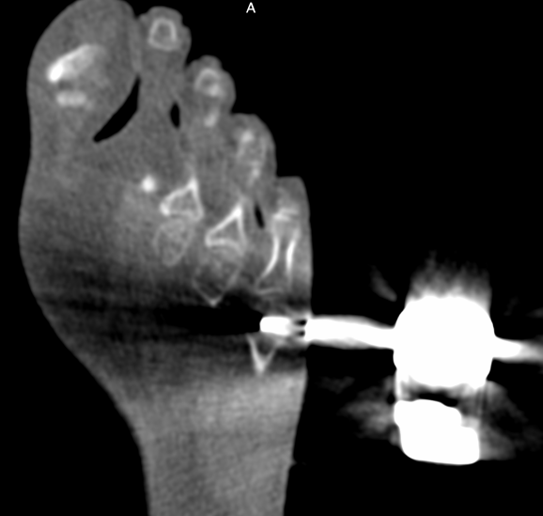

Cryoablation of the in the head of the fifth metatarsal

A 21-year old female presented with typical nocturnal foot pain partially relieved by aspirin, ultimately diagnosed with an osteoid osteoma of the fifth tarsal bone. Imaging confirmed a sclerotic lesion with a nidus and associated bone marrow edema. The patient was treated with CT-guided cryoablation using CAS-One IR. This included planning and navigation, as well as holding and guiding a bone drill. Despite a minor skin-related complication, the procedure resulted in complete resolution of nocturnal pain and radiological resolution of bone marrow edema at three months, with only mild residual soft tissue changes.

X-ray of the foot showed a sclerotic area with a visible nidus

MRI confirmed the lesion in the fifth tarsal bone with associated bone marrow edema